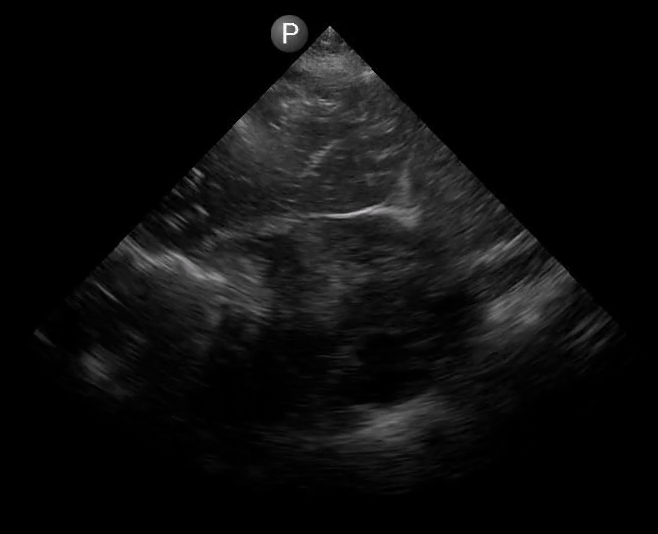

Definitions of cardiac activity and standstill vary across the literature. [14] Most definitions describe ventricular contractility and a decrease in left ventricular chamber size, though discrepancies exist with the identification of atrial or valve flutter. Ultrasound operators may also mistake movement of the chest structures with mechanical ventilation as cardiac activity. Furthermore, weak myocardial contraction, profound bradycardia, or fine ventricular fibrillation can also be confused as cardiac standstill. Examples of cardiac standstill and a weak, bradycardic rhythm are highlighted in Figure 2.

Figure 2. A) Parasternal long view with cardiac standstill. B) Subxiphoid view highlighting weak cardiac activity.